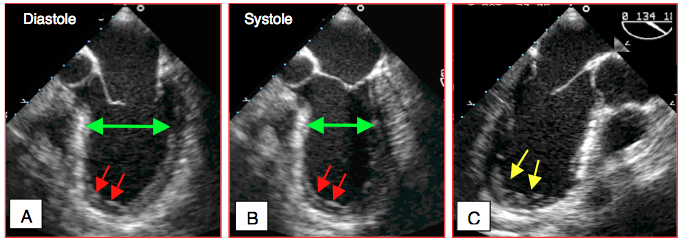

- 4 - Akinésie ; absence d’épaississement, paroi inerte ; diminution du flux coronaire à 5-10% de la norme, infarcissement de > 35% de l’épaisseur de paroi. La zone immobile peut apparaître plus importante que celle qui est réellement ischémiée à cause de la traction effectuée sur le voisinage par la région akinétique (tethering effect). Une akinésie de la région apicale se traduit typiquement par un apex dilaté et arrondi en vue 2-cavités et long-axe (Vidéos et Figure 27.22).

Figure 27.22 : Akinésie apicale. A et B: akinésie antéro-apicale (flèches rouges); cette zone n'a pas bougé entre la diastole (A) et la systole (B), bien que le diamètre septo-latéral (flèche verte) se soit rétrécit en systole (valve mitrale fermée) grâce au déplacement radiaire adéquat de la paroi latérale et modeste du septum. C: l'apex est dilaté et arrondi (flèches jaunes) en vue long-axe, alors que sa configuration anatomique normale est pointue.